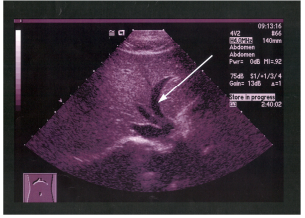

61 附圖為右上腹部縱向超音波掃描,箭號所指的構造為: (A)肝外膽管(extrahepatic bile duct) (B)肝內膽管(intrahepatic bile duct)(C)肝靜脈 (D)門靜脈

62 附圖中箭號所指的解剖結構為: